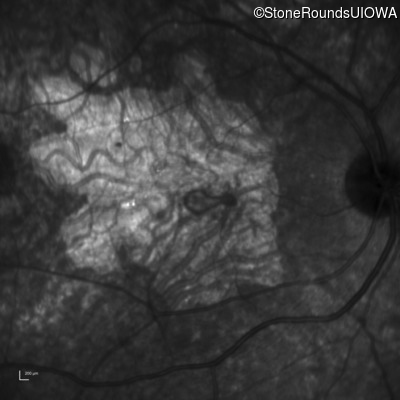

Age at visit: 30 years

This 30 year old man first noticed poor vision in dim light when he was five years old. His visual acuity began to fall in his early 20's.

Diagnosis & molecular findings

Macular Disease WDR19 His344Arg CAT>CGT Ser485Ile AGT>ATT AR